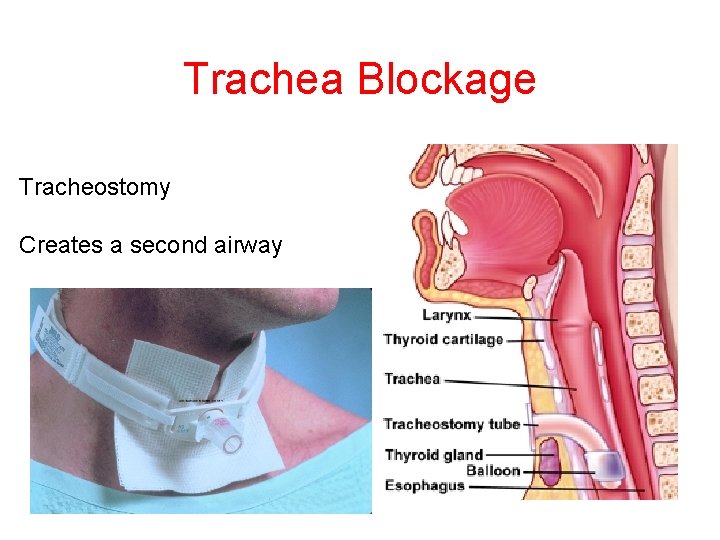

Trachea Blockage Tracheostomy Creates a second airway